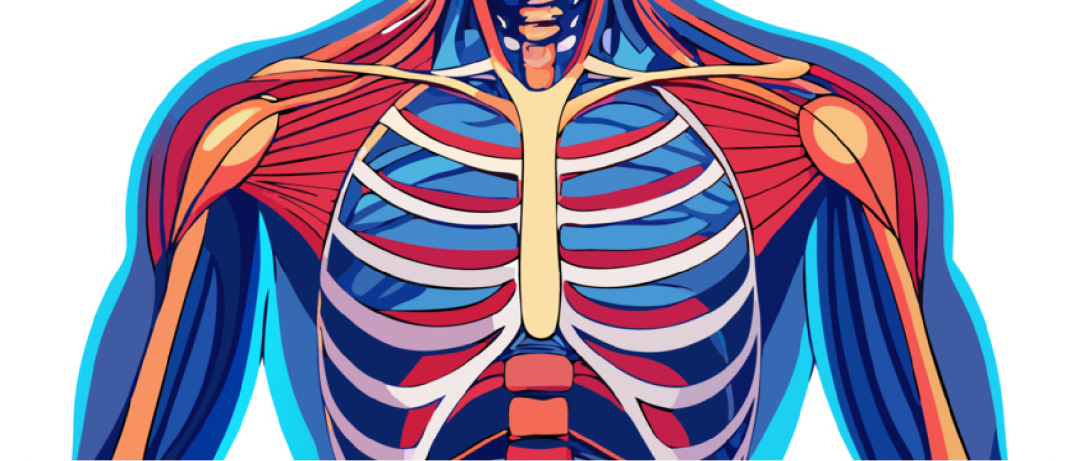

体感音波作用示意图

身体全域覆盖:通过骨骼与软组织传导,体感音波可从头到脚贯通全身,实现“动荡血脉、通流精神”的全身性生理疗愈和#心理疗愈 。体感音波的低频振动先穿透皮肤表层,再作用于皮下组织,进而渗透至筋膜,同时带动神经感知,实现能量的高效传递与深层作用,是体感音波“可触摸、深渗透”的关键所在。

体感音波对血液循环正向影响

促进血液循环:声音能量通过软组织传导的过程,会对人体血液循环产生显著的正向影响,相较于日常状态可实现3.5-4倍的提速。当低频振动依次穿透皮肤、皮下组织、筋膜时,会以谐振的方式,温和刺激皮下组织中的微小血管,带动血管轻微扩张,进而加速局部带动全身的血液循环。既契合中医“气血通畅”的理论,也符合现代绿色疗愈#健康护理 的需求,体现了秉航自研体感音波“非侵入、无负担”的核心优势。